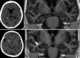

Cysticercus

Cysticercus (pl. cysticerci) is a scientific name given to the young tapeworms (larvae) belonging to the genus Taenia. [Source: Wikipedia ]